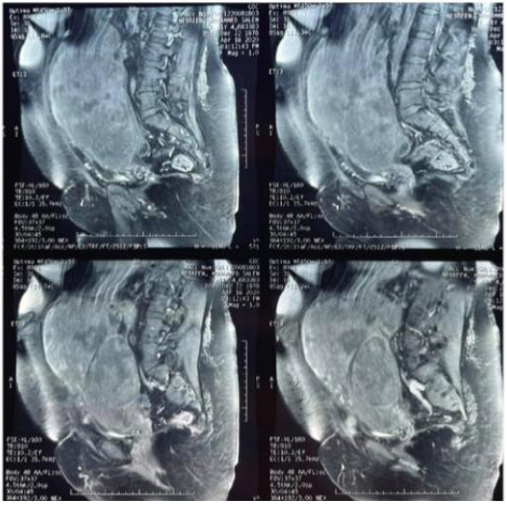

Investigations, Magnetic resonance Imaging (MRI) scan findings were suggestive of a large Lobulated masses compressing intestinal loops , arising from the uterine stump and extending into the abdomen, measuring 30×24 x 13 cm, adherent to both bowel and bladder (Figure 2) (Figure 3). CA125 was 132.3ng/mL (0-35ng/mL), LDH was 1127 (140-280U/L), the remain results were normal, and the patient was prepared for Mid-line exploration.

Figure 2 MRI of the Tumor before surgery.

Figure 3 MRI of the Tumor before surgery.

Pre-operative MRI with contrast for abdomen and pelvis is highly recommended to exclude abdomen metastatic sarcoma if the tumor is confined to the pelvis only.